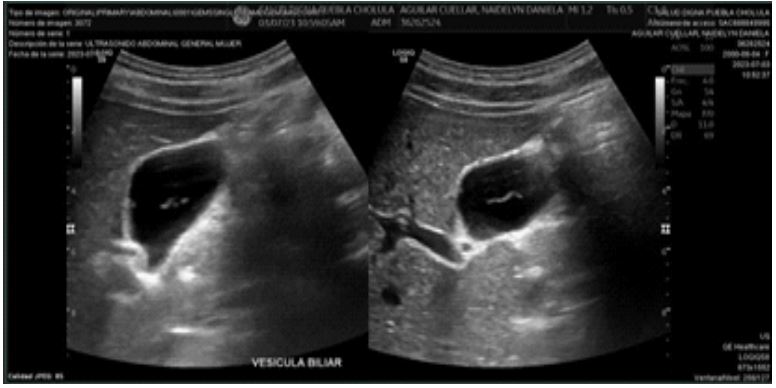

Subsequent control ultrasound reported:

- Gallbladder: Normal shape and contours, dimensions 57x21x24 mm (longitudinal, anteroposterior, transverse). Volumes: 17.7 cc. Thin wall (1.9 mm) heterogeneous due to a localized image at the body and anterior wall measuring 2x1 mm, hyperechoic, homogeneous, solid, regular contours, avascular.

Conclusion: Small polyp inside the gallbladder. No other abnormalities noted in this study (Figure 2).

Figure 2: Control ultrasound without alterations.